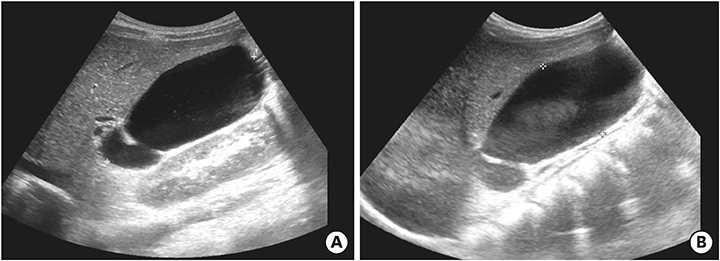

On the first day after admission, he received 2 g/kg IVIG and 50 mg/kg/day aspirin, following which his fever subsided and no further IVIG treatment was needed. His first echocardiography showed myocarditis (ejection fraction [EF], 45%) and mild ectasia of left main coronary artery (3.2–3.4 mm in diameter). On the second day after his admission, echocardiography (second follow-up) showed improved mild myocarditis (EF, 55%), improved ectasia of left main coronary artery (2.7–2.8 mm in diameter), and severe GB distension (8.9×4.6 cm in size), which possibly indicated GB hydrops (Fig. 2A). On the fourth day after his admission, although he had no fever and exhibited improvements in KD symptoms (i.e., eye injection, rash on abdomen, and cervical lymphadenopathy), he still complained of abdominal pain, distension, and tenderness of the RUQ. Follow-up laboratory findings were improved: neutrophilic leukocytosis (6,130 cells/mm3, with 33% neutrophils); decreased CRP (4.4 mg/dL), BNP (347 pg/mL), AST (40 U/L), and ALT (72 U/L); and improved hyperbilirubinemia (total bilirubin, 0.7 mg/dL). Echocardiography (third follow-up) showed normal completely improved carditis and still severe GB distension (10.2×5.5 cm in size) (Fig. 2B). Abdominal ultrasonography (US) was performed, which showed a markedly distended GB without stone, sludge, or wall thickening as well as normal bile ducts and liver morphology, which confirmed GB hydrops (Fig. 3A). On the sixth day after his admission, although his signs of KD had nearly disappeared, he still complained of abdominal discomfort, which had been moderately improving. The second follow-up abdominal US revealed a no notable change in GB distension compared to previous sonographic findings (Fig. 3B). An abdominal computed tomography (CT) scan was also obtained to exclude other hepatobiliary abnormalities, which showed similar findings as sonography, including a marked dilatation of the GB (8.0×5.5 cm in size) without stone, sludge, or wall thickening as well as normal bile ducts and liver morphology (Fig. 4). No complications necessitating surgical intervention had occurred and he was discharged 7 days after admission with only mild tenderness on the right upper-mid quadrant.

Fig. 3

Abdominal ultrasonography showed severe gallbladder distension (A) 9.8×4.9 cm in size and (B) 9.3×4.3 cm in size.